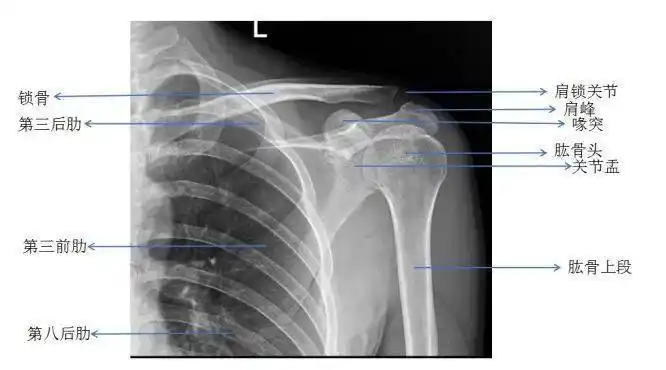

肩关节正位

图片尺寸501x318